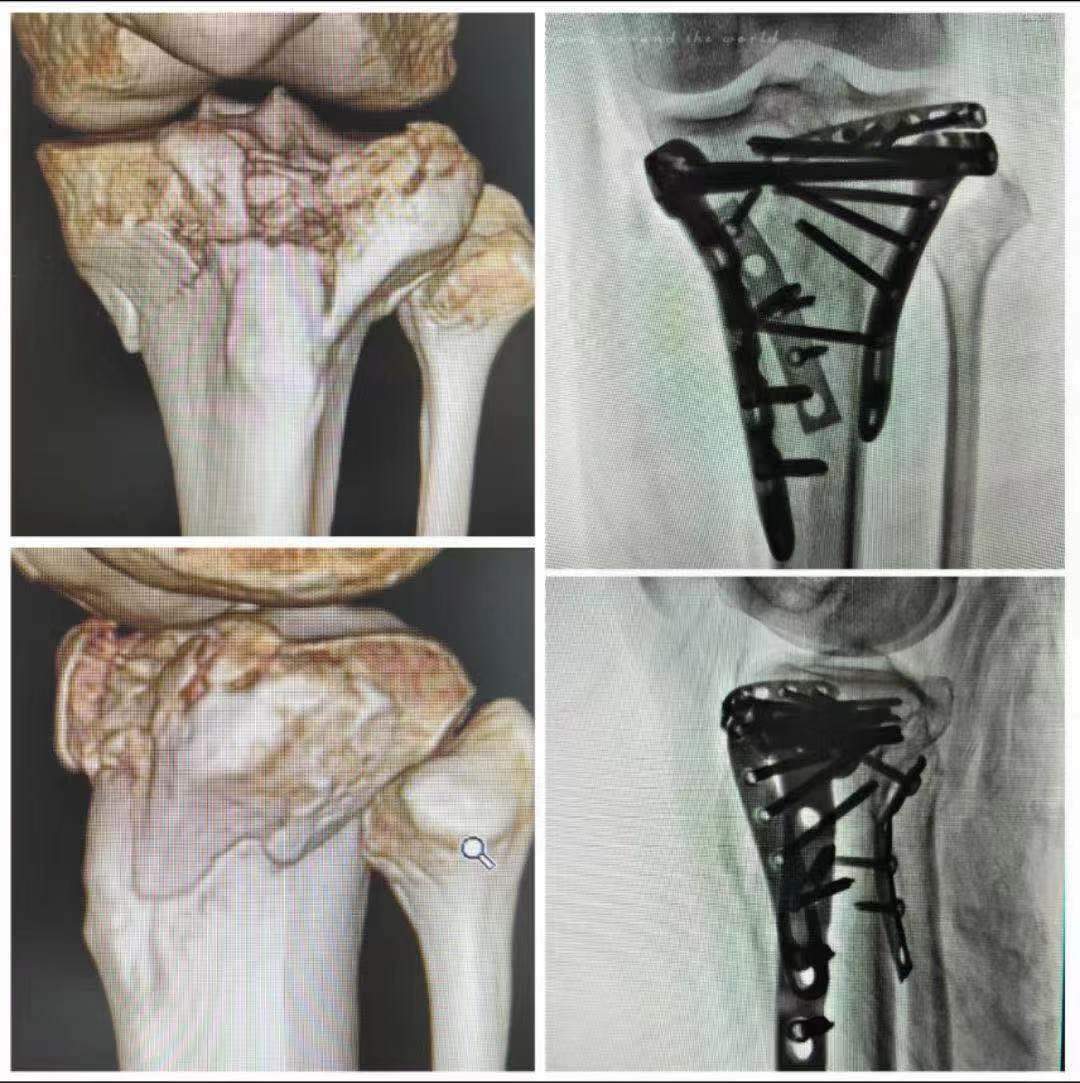

本次直播中,华兴一主任精选了创伤骨科领域最具备代表性的病种进行了手术演示,团队成功演示一例过伸型胫骨平台骨折切开复位内固定术和一例浮肩损伤切开复位内固定术。本次直播过程圆满顺利,所演示手术操作规范、入路清晰,线上交流活跃,充分展示了我院创伤骨科的实力。